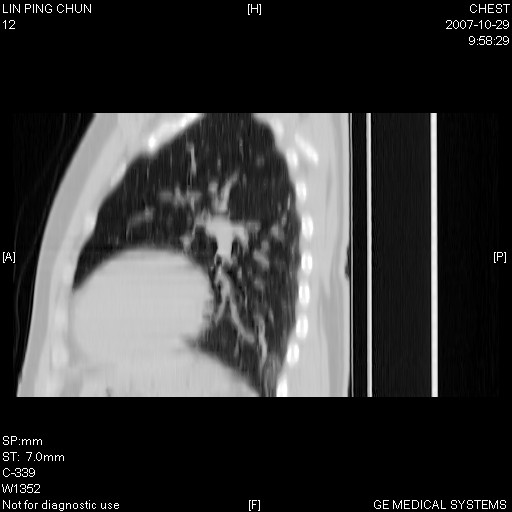

谢谢大家!!!上传纵隔窗,请大家帮我分析。

左下肺后基底段磨玻璃样影,很多病都可以。不能吊以轻心。应该做局部增强hrct进一步检查,并严格抗炎治疗后复查或经皮活检。

左下肺后基底段小斑片泪膜玻璃样影,其内可见空泡影,边缘可见小毛刺影。建议抗炎治疗复查,肿瘤待排

老兄,我建议您把病灶做个薄层处理,靶重建,然后上传过来,您仔细看看现在的病灶特点,小病灶,边界清,内见空泡征,高度警惕细支气管肺泡癌,最好的结局就是aah(不典型性腺瘤样增生).我会密切关注您的.另外,现在您可正规抗炎治疗半月后,与3个月后复查观察病灶变化,如没有太大变化,我建议您立即手术,放心!即使是肺癌也是早期,不会影响您的生命的,祝您好运.